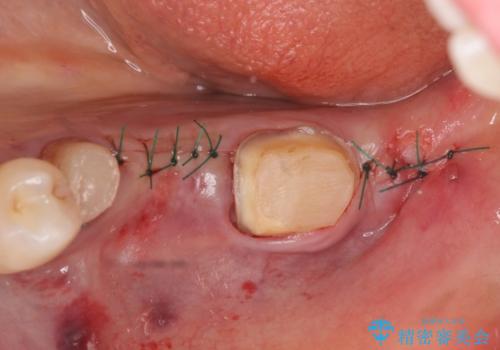

左下7の遠心部は部分的な骨欠損によるポケットが10mmあったため、再生療法による骨の再生を行いました。

骨の定着を待ちポケットが3mm(正常範囲内)であることを確認後、オールセラミッククラウンによる欠損補綴を行いました。

再生療法とは歯槽骨の欠損部位を人工骨で補うことにより骨を再生させる手術です。

この手術を行うことで、歯周基本治療では治癒しない歯周病を改善したり、本来ならば抜歯しなければならない歯を保存することができます。